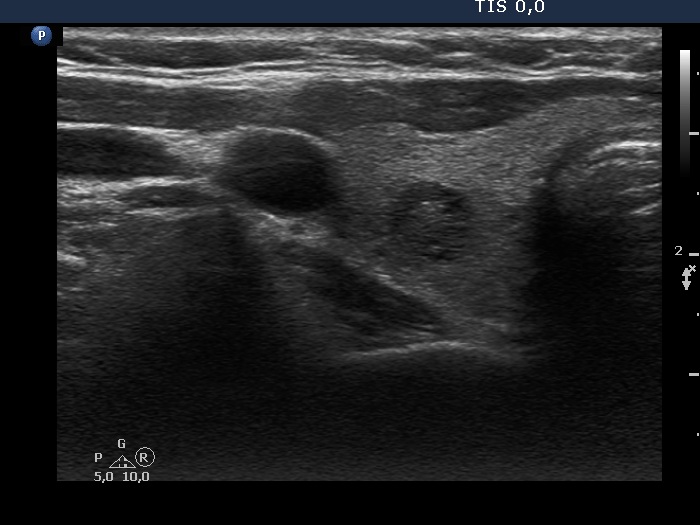

Clinical presentation: A 58-year-old woman was referred for evaluation of a nodular goiter which was discovered on ultrasound screening.

Ultrasonography. The thyroid was echonormal. Beside tiny hypoechoic areas, two larger lesions were found in the right lobe, a moderately hypoechoic and a cystic one.

Cytology of the moderately hypoechoic lesion resulted in benign cystic-colloid goiter.